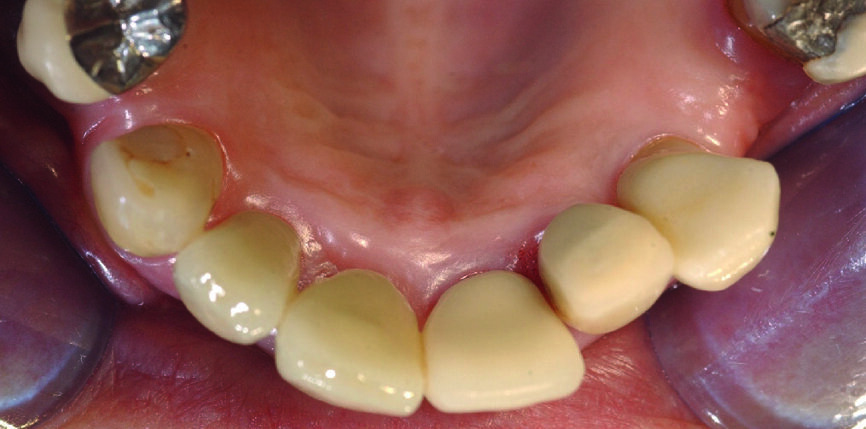

Figs. 11a & b : Vues cliniques et occlusales des scan bodies en place. Notez les positions et les axes obtenus, qui faciliteront les réalisations prothétiques définitives.

Des scan bodies (Core 3D), correspondant aux implants, sont positionnés et les empreintes optiques réalisées avec la camera 3Shape (Figs. 11a et b). A ce stade, il est fortement recommandé de faire une radiographie de contrôle, afin de vérifier le bon enfoncement des scan bodies et pour éviter toute erreur, qui se répercuterait au niveau de la prothèse (Fig. 12).